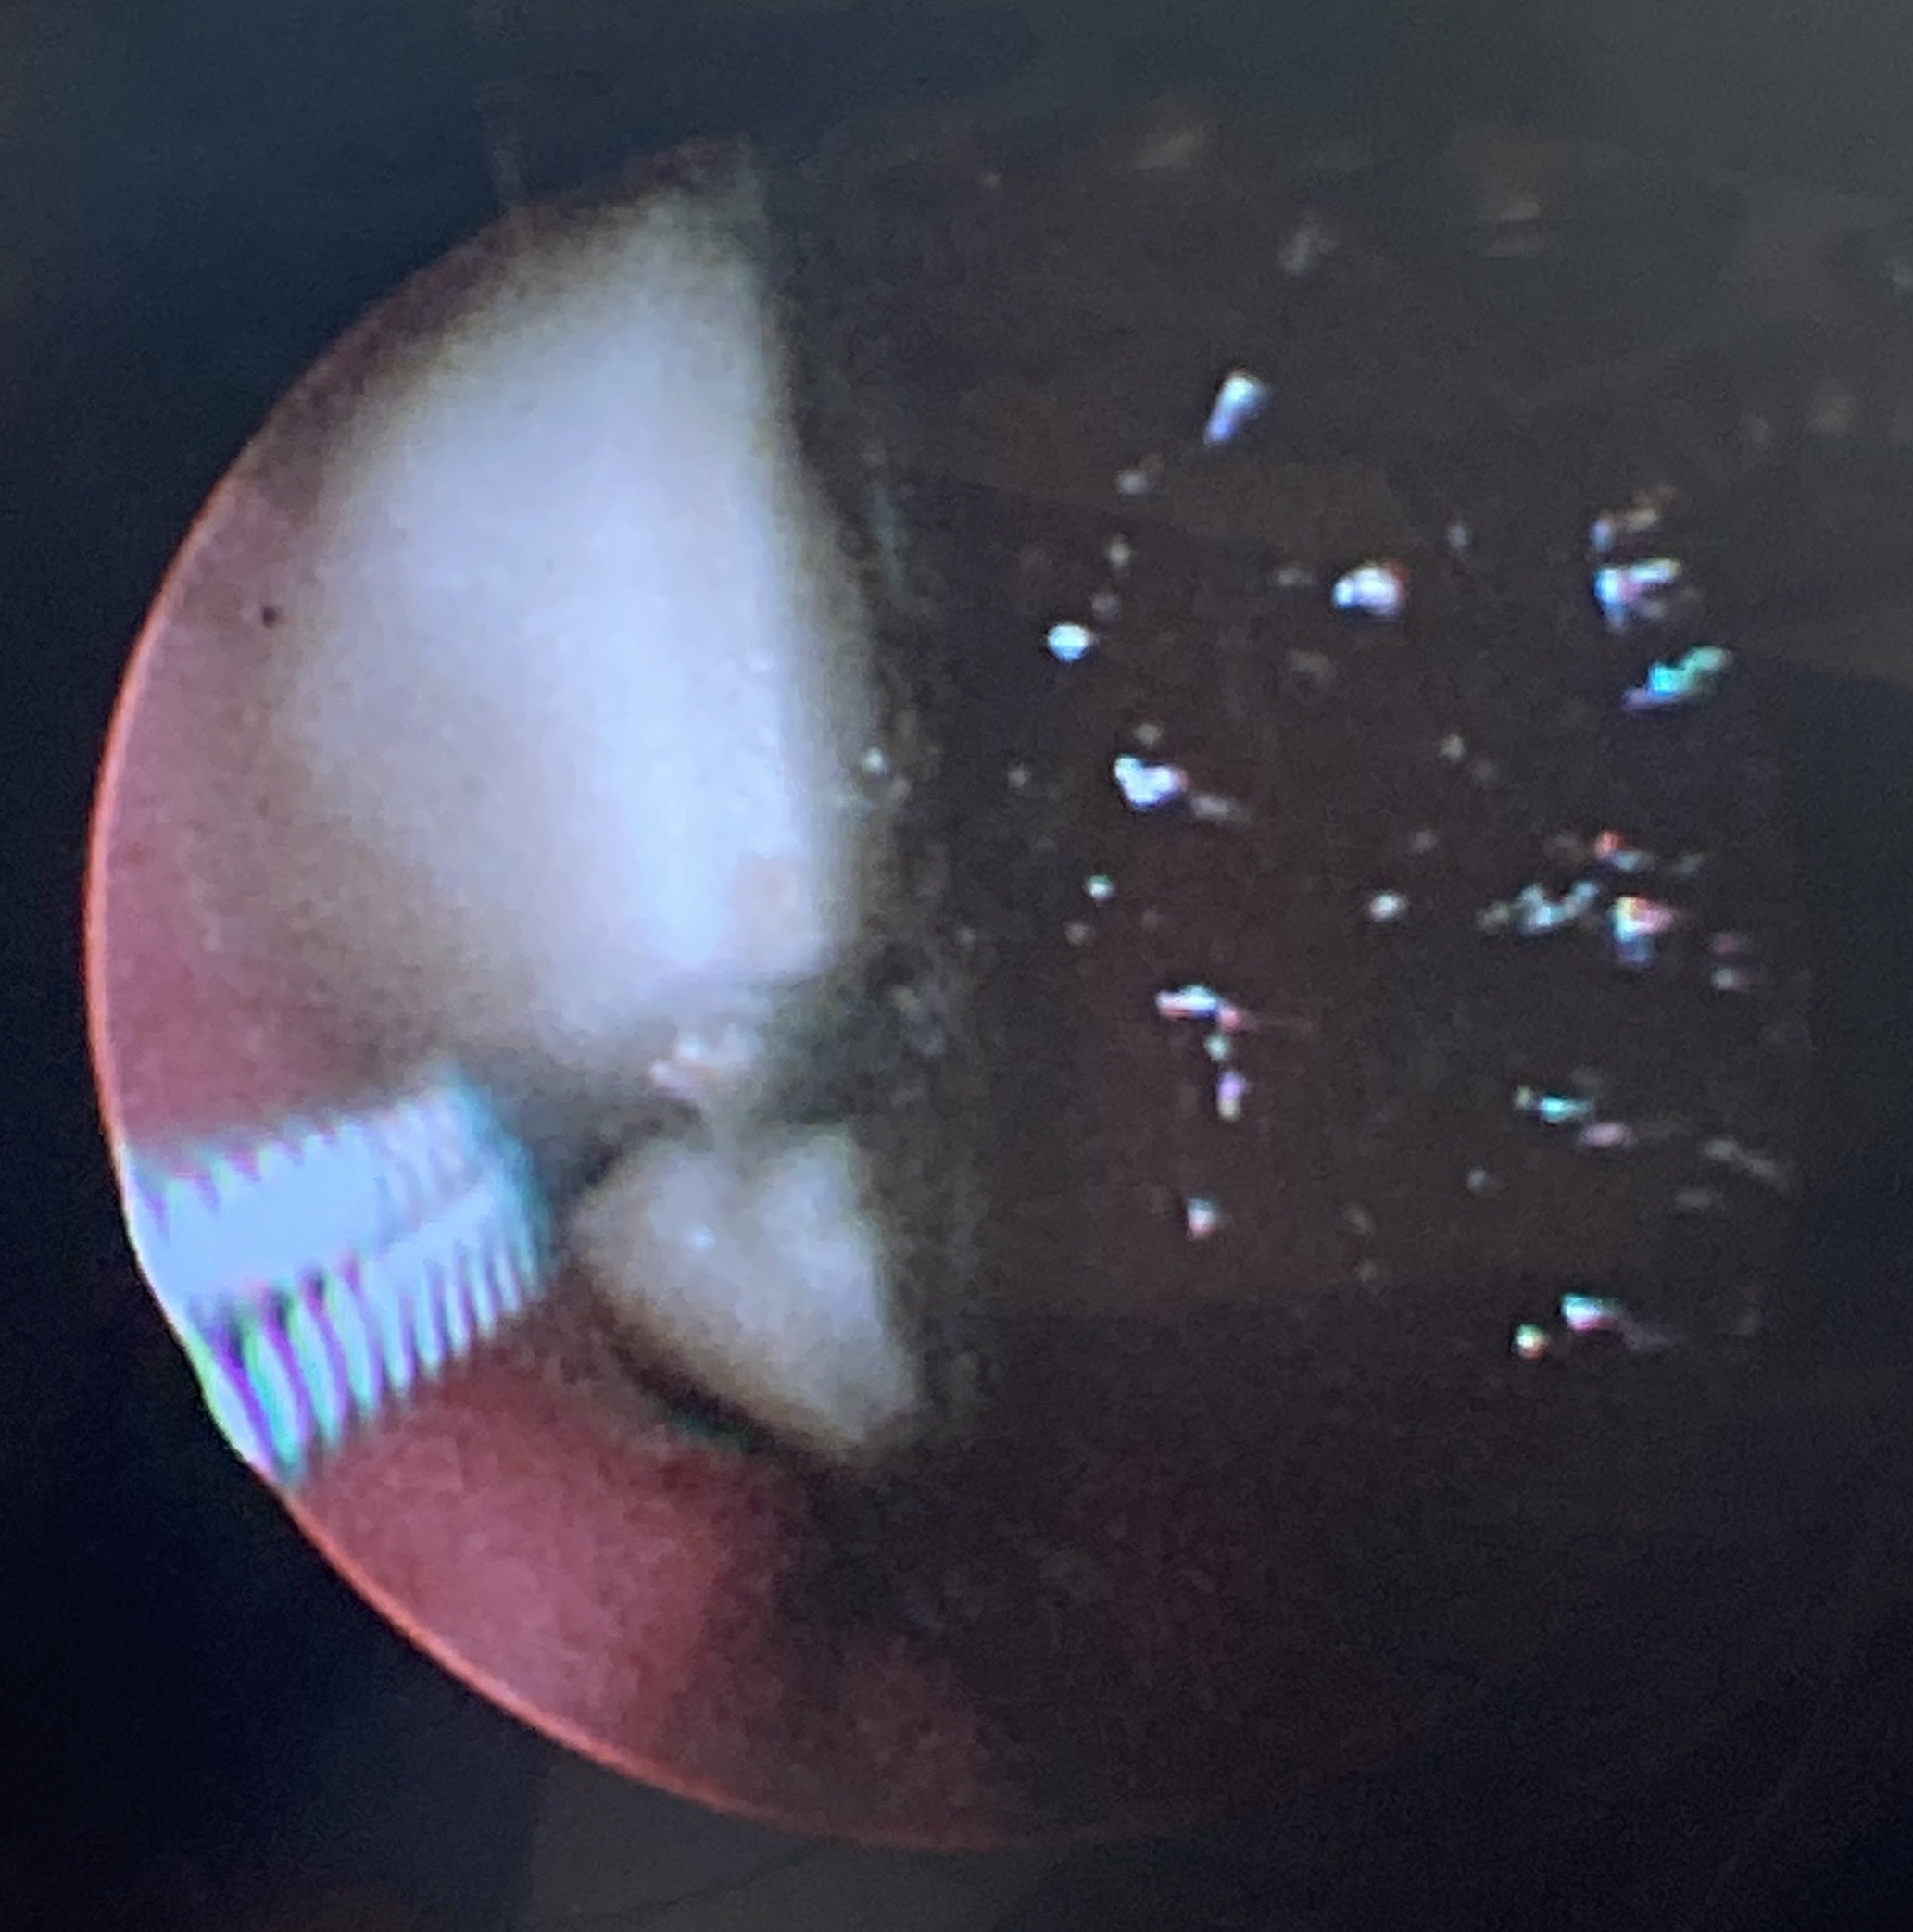

この画像は丸い白い異物を飲み込んだフレンチブルドックの内視鏡画像です。催吐処置を行なっても吐出できなかったため、内視鏡での摘出を試みました。胃の中で白い物体を内視鏡の把持鉗子で掴んでいるところです。

内視鏡処置で無事摘出できたため、開腹手術をしないで済みました。水回りの何かの部品だった様です。直径3cm程度の丸い薄いものだったため、飲み込めたけれども、吐出はできなかった様です。放置すれば、腸で詰まっていた可能性があります。